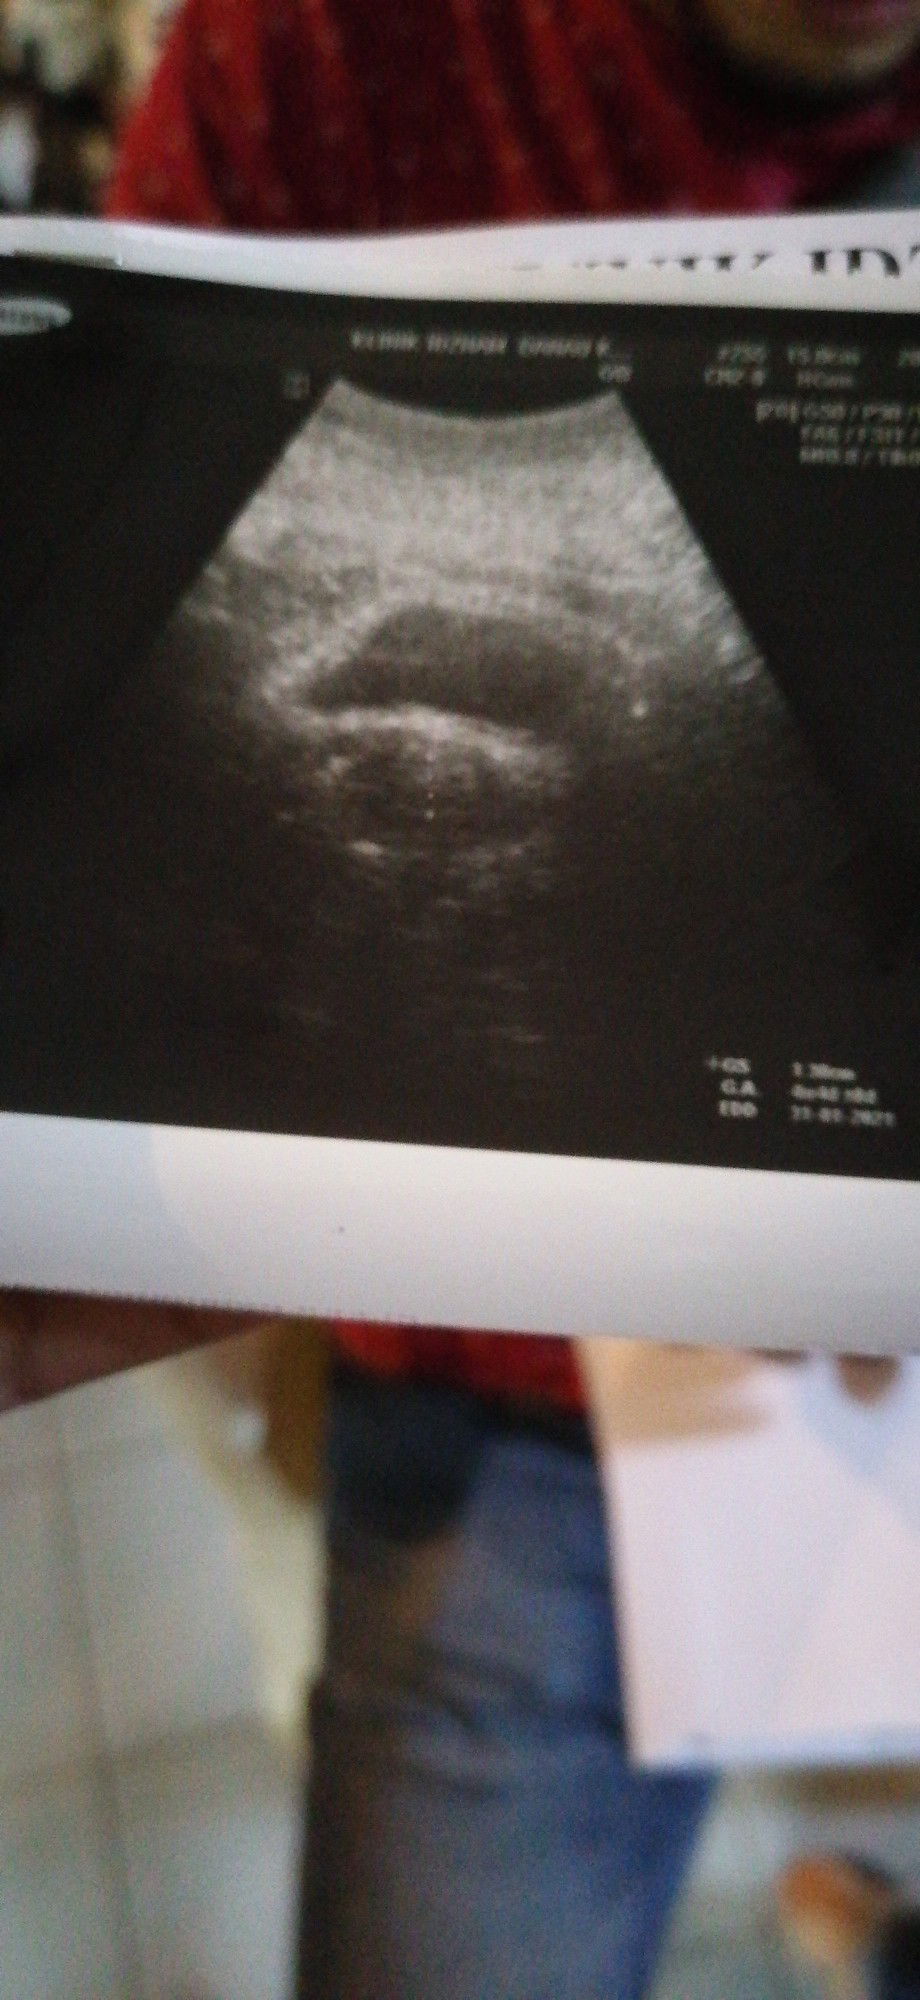

sy buat test upt kabur.. lepas 3hri bleeding sikit.. jadi pg sca tak nampak ape2.. lepastu pergi klinik repeat scan mcm gambar dibawah. m pergi hospital doct 1st scan kate kemungkinan ectopic.. kene tahan wad ambik drh.. 2nd doct. just berpandukan ujian darah kate beta hcg rendah 200++ jadi consider tak. pregnant..die.suruh balik.. masalah yg sy nampak.time.scan tu ape benda.. musykil dan xthu nk buat ape